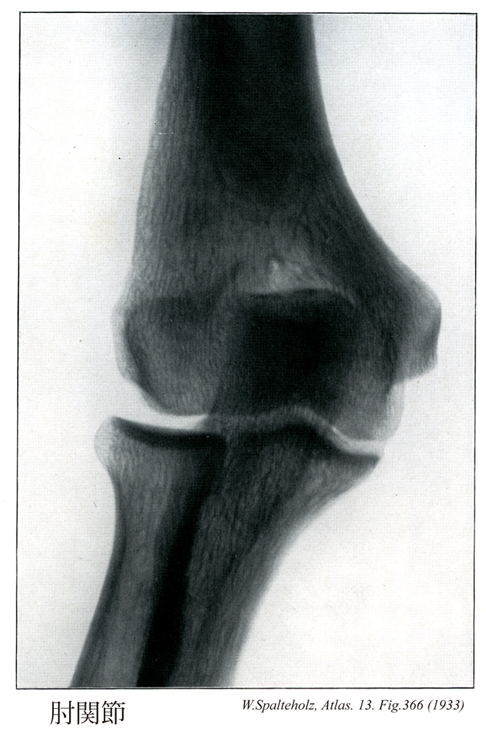

366_00【Elbow joint肘関節 Articulatio cubiti】 Joint formed by the humerus, radius, and ulna. →(肘関節は上腕骨と橈骨、尺骨の3骨の間に生じた複関節で、肘の屈伸を行う。したがって分類状は1軸性の蝶番関節とみることができる。上腕骨滑車と尺骨の滑車切痕との間の腕尺関節、上腕骨小頭と橈骨頭との間の腕橈切痕との間の上頭尺関節が共通の関節包におおわれる。しかし後者は機能的には下橈尺関節とともに前腕の回旋に関係するので、前2者とは別に記載するのが通例である。上腕骨の内側および外側上顆は関節包におおわれない。関節包の内側と外側はそれぞれ内側側副靱帯および外側側副靱帯によって補強される。橈骨輪状靱帯は、関節包の内面が肥厚した幅約1cmの靱帯で、尺骨の橈骨切痕の前縁からおこり、橈骨の関節環状面を輪状にとりまいたのち、再び尺骨の橈骨切痕の後縁につく。この靱帯の関節腔に面した部分は軟骨性となり、尺骨の橈骨切痕とともに上橈尺関節における関節窩を形成する。肘関節における屈伸運動の役割を演ずるのは腕尺関節である。しかし上腕骨滑車の内側部の直径が外側部のそれよりやや大きいため、肘を伸ばすと、その時の尺骨の長軸は、上腕骨長軸よりも外方へ約10~20°の傾きを示す。この角をcarrying angleという。しかし肘を曲げたときは、両骨の長軸は重なり合う。)